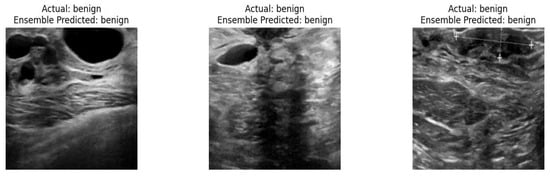

- We consider an ensemble of multi-stage transfer learning models such as DenseNet 121, Inception-V3, and XceptionLike for classifying breast tumor images.

3.2. Ensemble-Based Multi-Stage Deep Transfer Learning Model